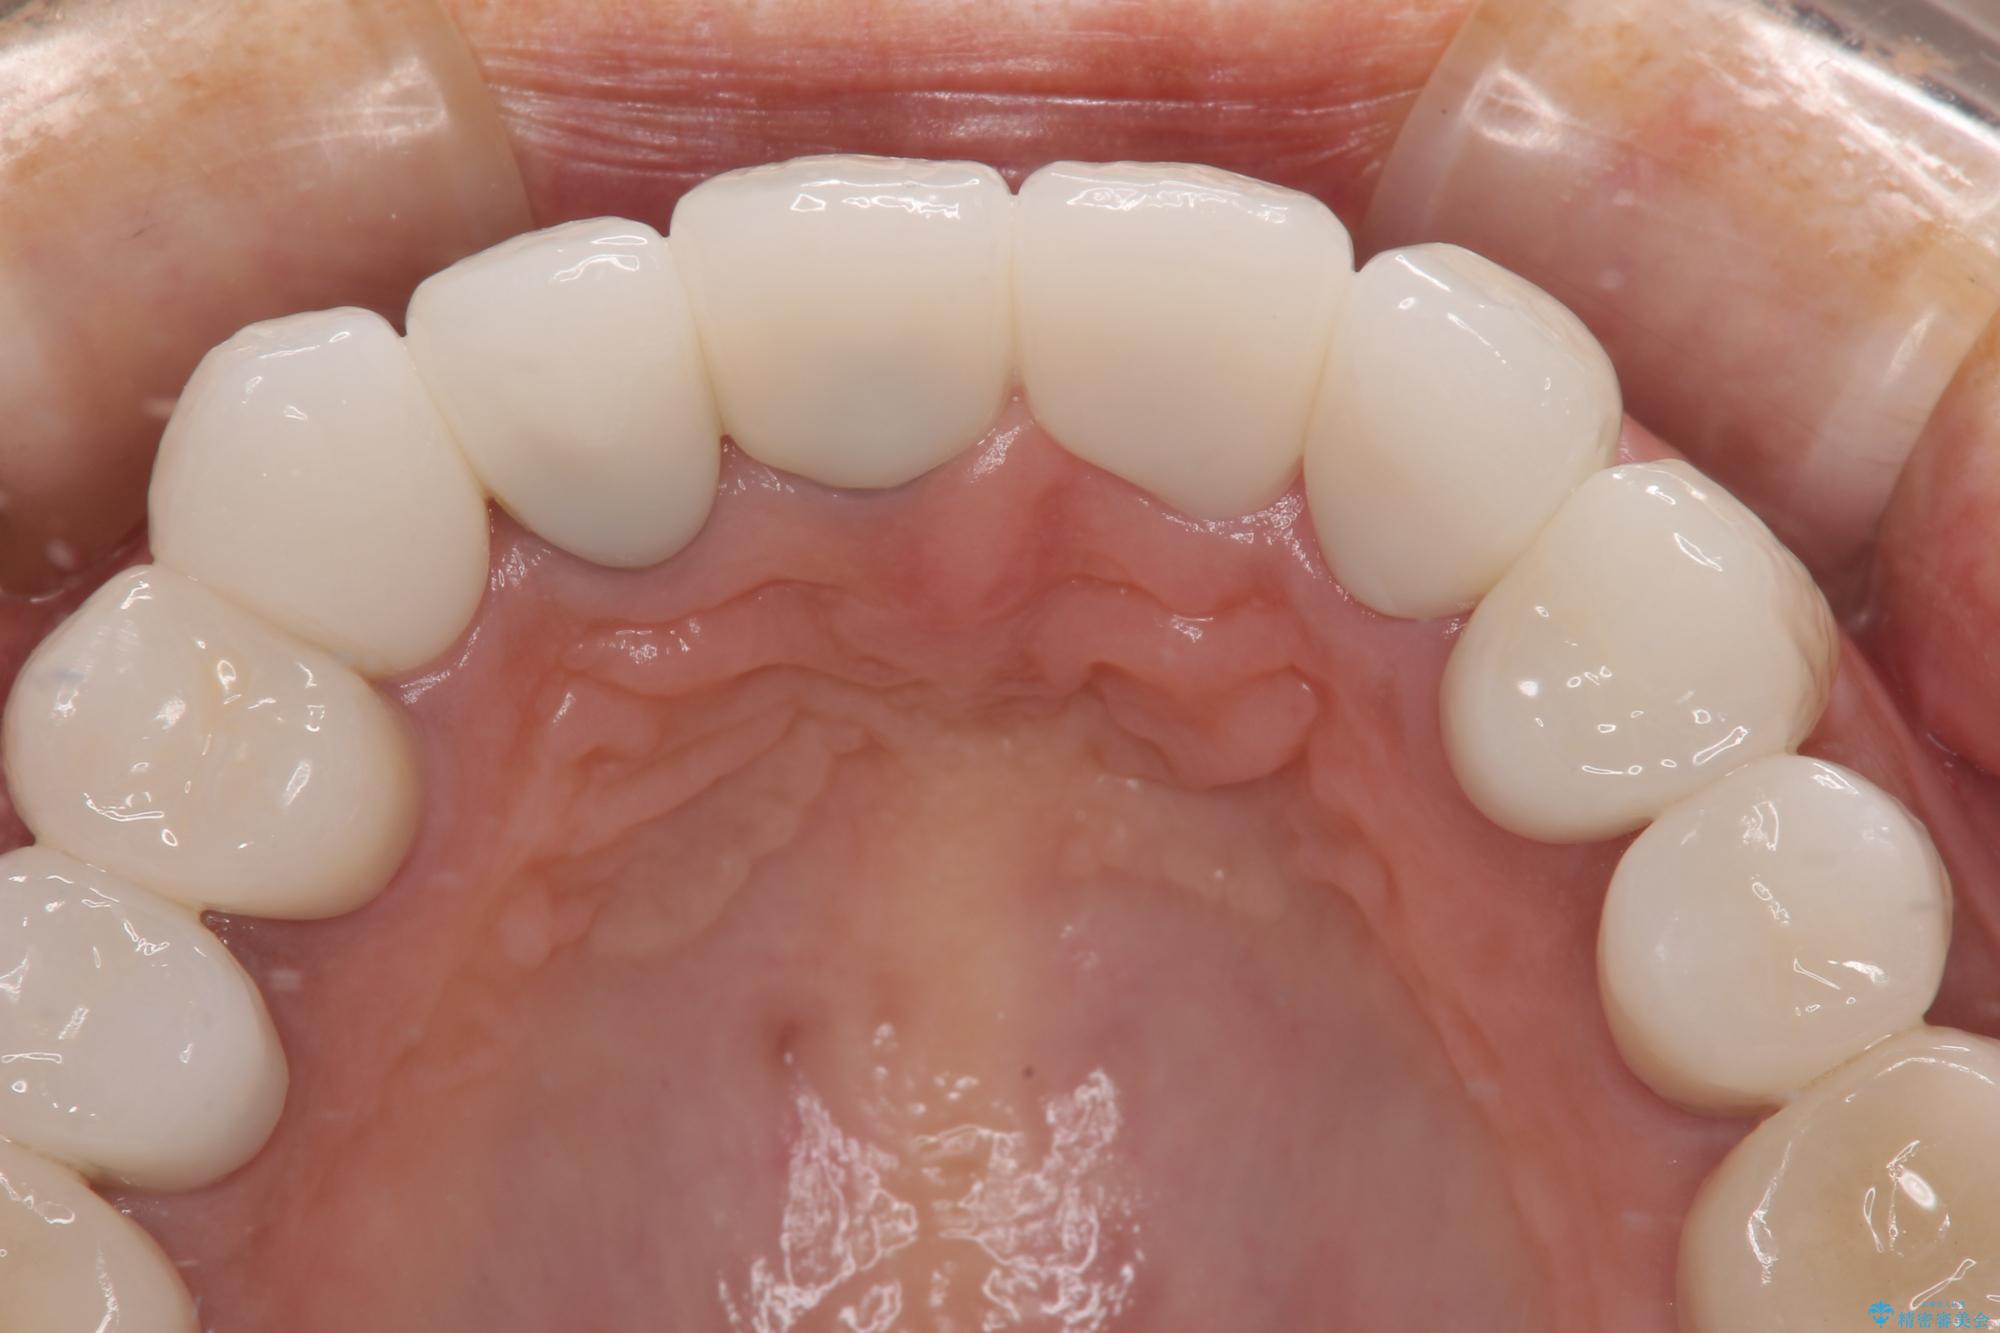

20年以上前から、むし歯になったり詰め物が欠けたりする度に部分的に処置を行ってきたそうですが、この際統一感のある前歯にしたいとのことで、上顎前歯9本をオールセラミッククラウンによる補綴治療を行うこととしました。

色調が統一されるだけでなく、歯肉ラインに見えていた茶色の境目も綺麗に改善されました。